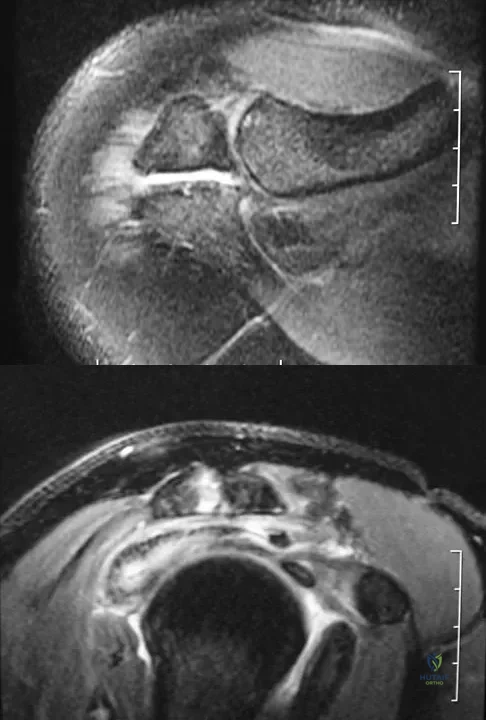

A 74-year-old woman has had acute medial right knee pain for the past 3 months. She denies any history of trauma or previous problems. Coronal and sagittal MRI scans are shown in Figures 11a and 11b. What is the most likely diagnosis?

Explanation